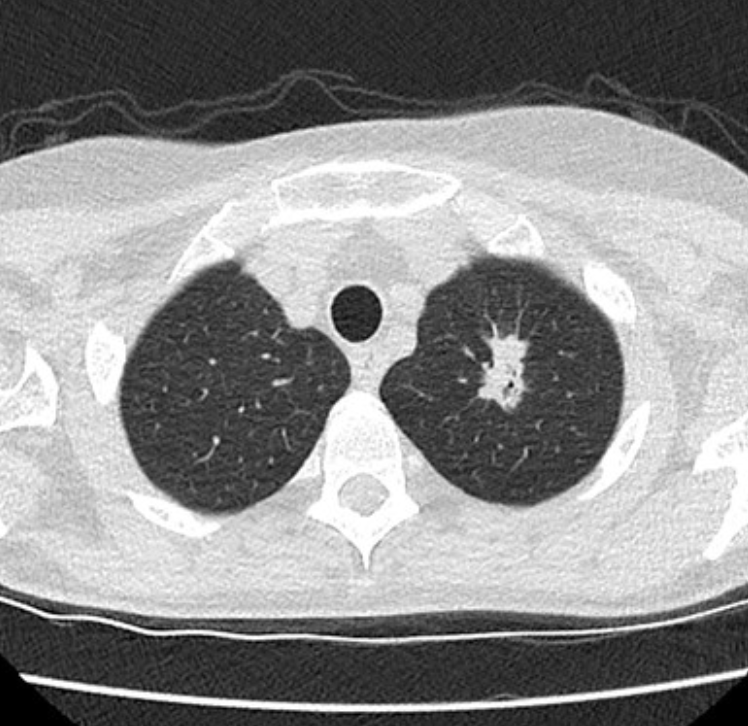

Computed Tomography (CT) scans are fast scans of the body with X rays. It will feel like you are moving through the donut over the course of seconds. A 3D image will be able to show doctors high resolution images of your bones and organs. Sometimes, iodinated contrast is injected into your veins prior to the scan to better show blood vessels and certain organs. Tumors tend to have leaky disorganized blood vessels because they grew in such a hurry, so contrast will leak through and show some tumors better.